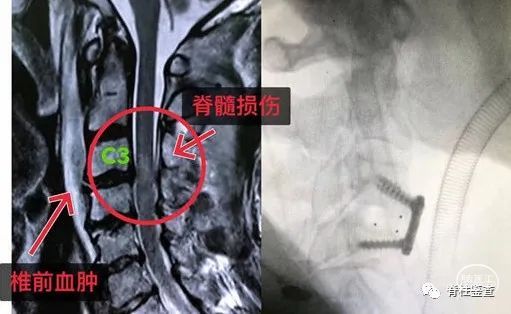

主诉:车祸后双上肢麻木

诊断:颈3-4关节绞锁脱位